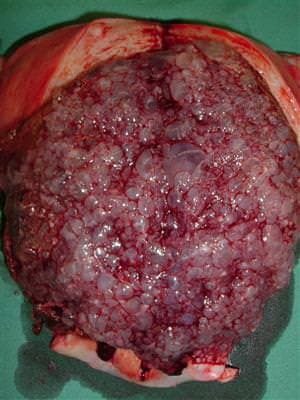

Trofoblastik hastalık; kadın yumurtasının, bir genetik kromozom bozukluğundan dolayı, spermle döllendiği zaman, gebelik ürününün normal bebek değil, üzüm şeklinde içi su dolu kesecikler şeklinde oluşmasıdır. Yani bozuk, anormal bir gebeliktir, ama bebek yoktur. En basit şeklinin tıbbi adı ‘mol hidatidiform‘dur ve “mol gebeliği” olarak adlandırılır.

Bazen, kanamayla birlikte üzüm şeklinde parçalar düşmeye başlar, o zaman tanı kolaylaşır. Zaten halk arasında bu hastalığa üzüm gebeliği denir. Bu parçalar düşmeden önce tanı ultrasonografi (USG) ile kolayca konabilmektedir. Ultrasonografide bebek görülemez ve kar fırtınası manzarası denen çok tipik bir görüntü vardır. Ayrıca kanda yapılacak gebelik testinde de çok yüksek bir değer bulunacaktır.